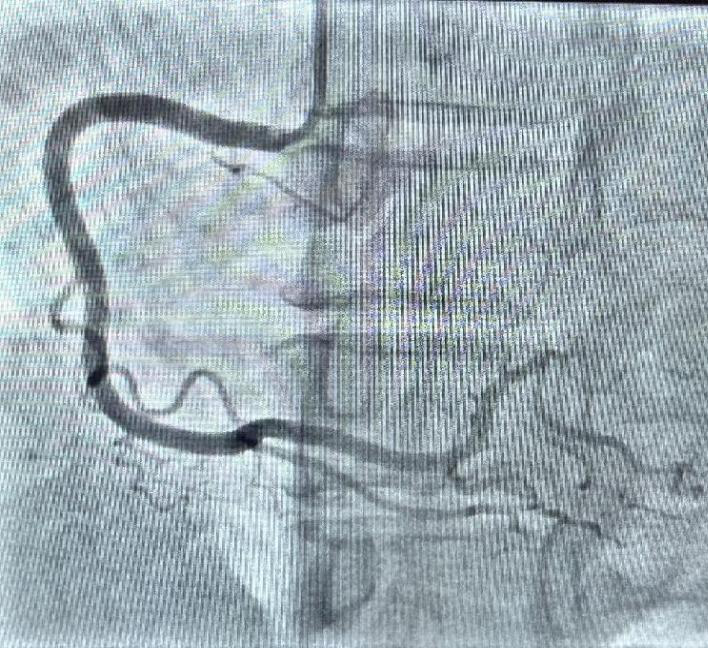

下肢动脉造影

数字减影血管造影的原理是将注入造影剂前后拍摄的两帧X线图像经数字化输入图像计算机,通过减影、增强和再成像过程来获得清晰的纯血管影像,同时实时地显现血管影。